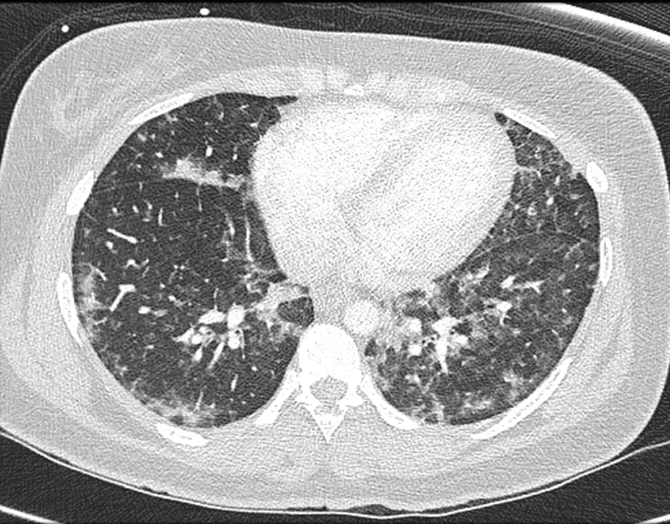

Patrick Natter, MD; Dinesh Rao, MD; Inbal Cohen-Rasen, MD; Paul L. Wasserman, DO; Dalys E. Haymes, MD; Sukhwinder Johnny S. Sandhu, MD; Austin Fischer, DO

This patient presented with findings that were suggestive of cerebral fat emboli (CFE) in fat embolism syndrome (FES).

03/15/2017